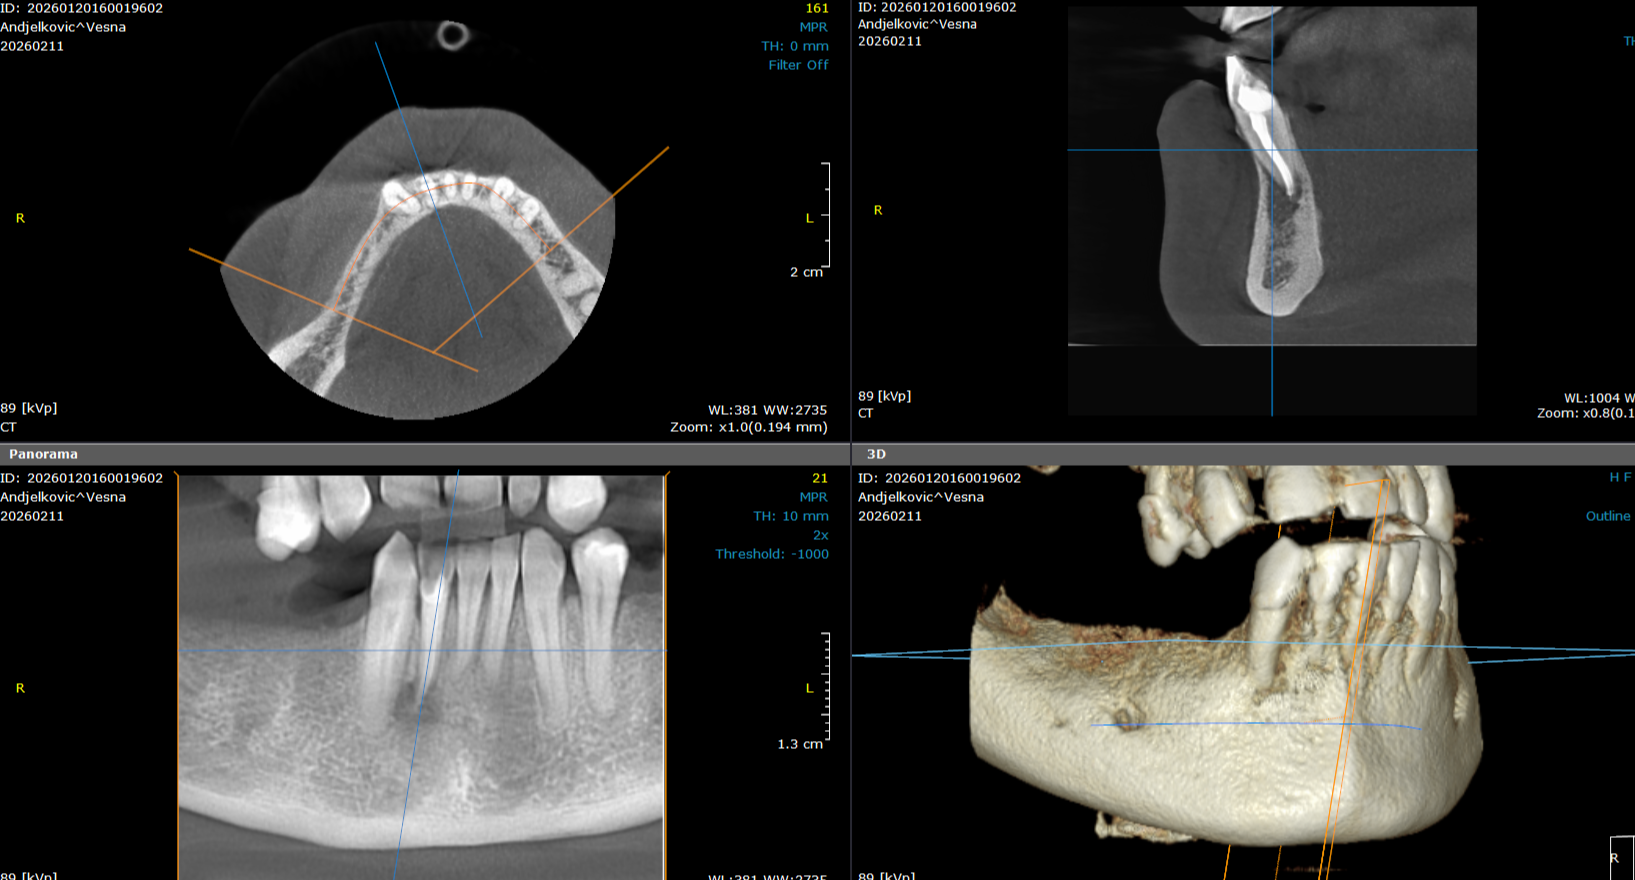

3d snimak - cbct obe vilice

3d snimak gornje i donje vilice je trenutno najkompletniji i najpouzdaniji snimak vilice, zuba i okolnih struktura. Koristi se u stomatološkoj dijagnostici za detaljan pregled, pri pravljenju plana za ugradnju implantata.

8 000,00 rsd

3d snimak - regije

3d snimak regije omogućava detaljan trodimenzionalan prikaz određenog dela vilice i zuba. Koristi se za preciznu dijagnostiku, planiranje implantoloških i hirurških zahvata, kao i za analizu stanja kosti i korena zuba.

4 000,00 rsd